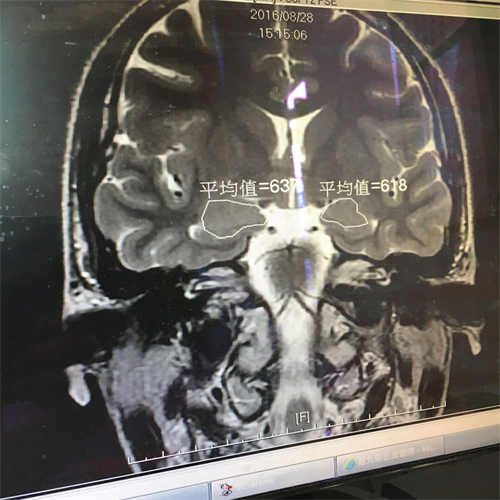

'图2:医院做核磁共振检查显示“脑部杏仁核肿大”。'

图2:医院做核磁共振检查显示“脑部杏仁核肿大”。